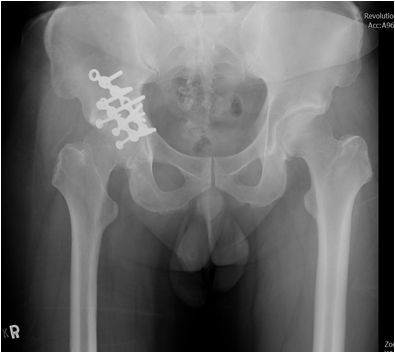

圖:手術治療前後的大腿股骨與髖關節。

而當時的主治醫師就是個性直率低調,被同事與後進同仁暱稱為鄺爺的骨科鄺世通醫師,這個在鄺醫師口中的小骨折,其實是包含髖關節、大腿股骨、膝蓋髕骨、與小腿脛骨等多處粉碎性骨折的複雜個案,不論是X光檢查,還是電腦斷層檢查,都能看見因為強力撞擊穿出髖關節的股骨,還有粉碎的髕骨,歷經數個小時的開刀,才救回洪國程先生的性命與右腿。

後來洪國程才知道,當時鄺醫師可以說是像是在拚一個摔破的瓷碗,一塊一塊地把他的骨頭拼回去,然後再細心的照顧他的傷口,才讓他免去截肢的痛苦,洪國程回想起來,心有餘悸的說:「當時我才35歲,正當年輕而且小孩還小,真的無法想像下半輩子要坐輪椅的生活。」